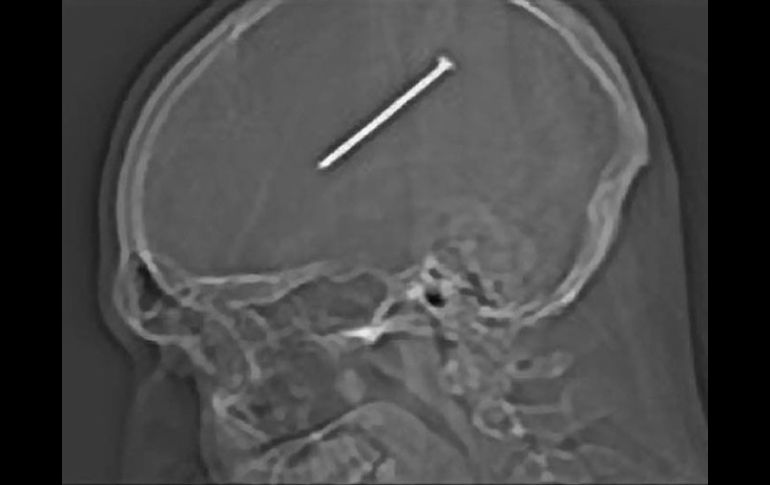

Entretenimiento | Dante Autullo se diparó por accidente el metal de 8.25 centímetros Hombre se introduce clavo en el cerebro por accidente en EU El hombre creyó sentir un golpe de la herramienta, pero lo que ocurrió en realidad es que la pistola reconoció su cabeza como una superficie plana y le disparó un clavo Por: AP 21 de enero de 2012 - 15:48 hs Radiografía del clavo de 8.25 centímetros en la cabeza de Autullo. AP / OAK LAWN, ESTADOS UNIDOS (21/ENE/2012).- Gail Glaenzer aún no puede creer que su prometido se haya disparado un clavo en el cráneo sin percatarse de ello, y mucho menos que haya publicado una imagen de rayos X en Facebook mientras iba en la ambulancia que lo trasladó de un hospital a otro para someterlo a una cirugía. Sin embargo, la mujer bromeó sobre el asunto el viernes, un día después de que los médicos le sustrajeron a Dante Autullo el clavo de 8.25 centímetros (3.25 pulgadas) que él mismo se introdujo en el cerebro. "Dante dice, 'Quiero hacer un collar con esto''', dijo Glaenzer, sentada el viernes en el vestíbulo del Centro Médico Advocate Christ, donde Autullo, de 32 años, fue internado en buenas condiciones en la unidad de terapia intensiva. La mujer seguía sin creer cuán afortunado era el padre de sus cuatro hijos. "Se siente bien. Podía mover todos sus miembros, habla normalmente, recuerda todo", dijo Glaenzer, de 33 años. "Es asombroso, un milagro". Autullo estaba en su taller el martes, utilizando su pistola de clavos, cuando la herramienta dio un culatazo cerca de su cabeza, dijo Glaenzer. El hombre creyó sentir un golpe de la herramienta, pero lo que ocurrió en realidad es que la pistola reconoció su cabeza como una superficie plana y le disparó un clavo, explicó Glaenzer. "Yo lo vi cuando llegó a casa, y parecía como si (su cabeza) tuviera una cortada", dijo la mujer. Autullo le explicó a su pareja que al parecer un clavo le había "rozado la cabeza, junto a la oreja". La mujer simplemente limpió la herida con agua oxigenada. Ninguno de los dos pensó mucho al respecto, y Autullo siguió con su día. Incluso paleó un poco de nieve. Pero al día siguiente, se despertó de una siesta y sintió náuseas. Glaenzer sintió que algo andaba mal y le sugirió a Autullo que fueran al hospital. Al principio Autullo se rehusó, pero accedió el miércoles, luego de que recogieron a un hijo del colegio. Un par de horas después se le tomó una radiografía, la cual reveló la presencia del clavo, a la mitad del cerebro. Los médicos le dijeron a la pareja que el clavo quedó a milímetros de la zona del cerebro que controla las funciones motoras. El portavoz del hospital Mike Maggio dijo que la cirugía llevó dos horas y la parte del cráneo que se removió para la operación fue reemplazada por una malla de titanio. El cirujano no quiso poner de vuelta la parte del cráneo por temor a que se hubiera infectado con el clavo. Temas Estados Unidos Ciencia médica Curiosidades Lee También "Streamer" transmite su parto en vivo y causa revuelo en redes sociales INAPAM: ¿Cómo solicitar un turno para consulta médica gratuita? ALERTA en Jalisco por formación de ciclón "Raymond" Esta es la última guerra que Trump resolvió, según él mismo Recibe las últimas noticias en tu e-mail Todo lo que necesitas saber para comenzar tu día Registrarse implica aceptar los Términos y Condiciones